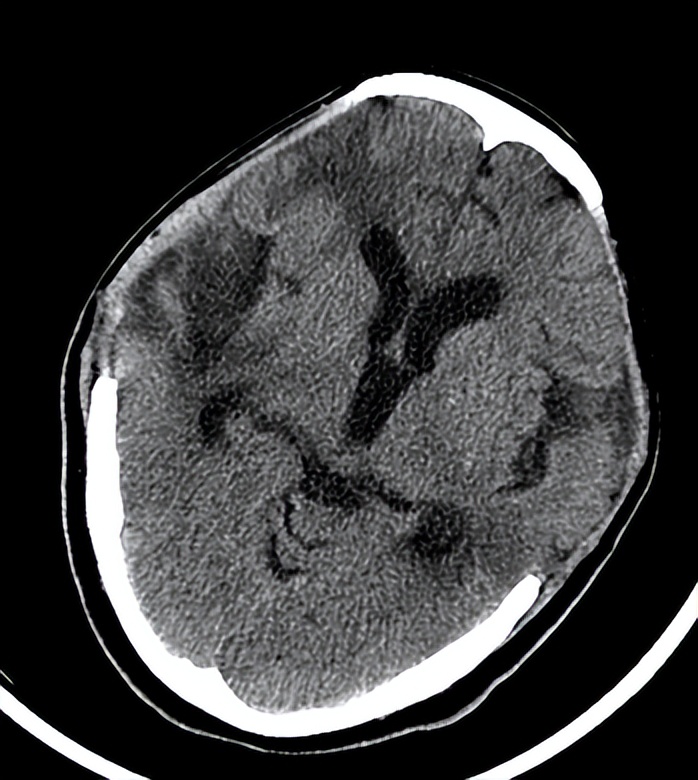

06-07日入院时头CT

06-07 21:30术后复查头CT示: